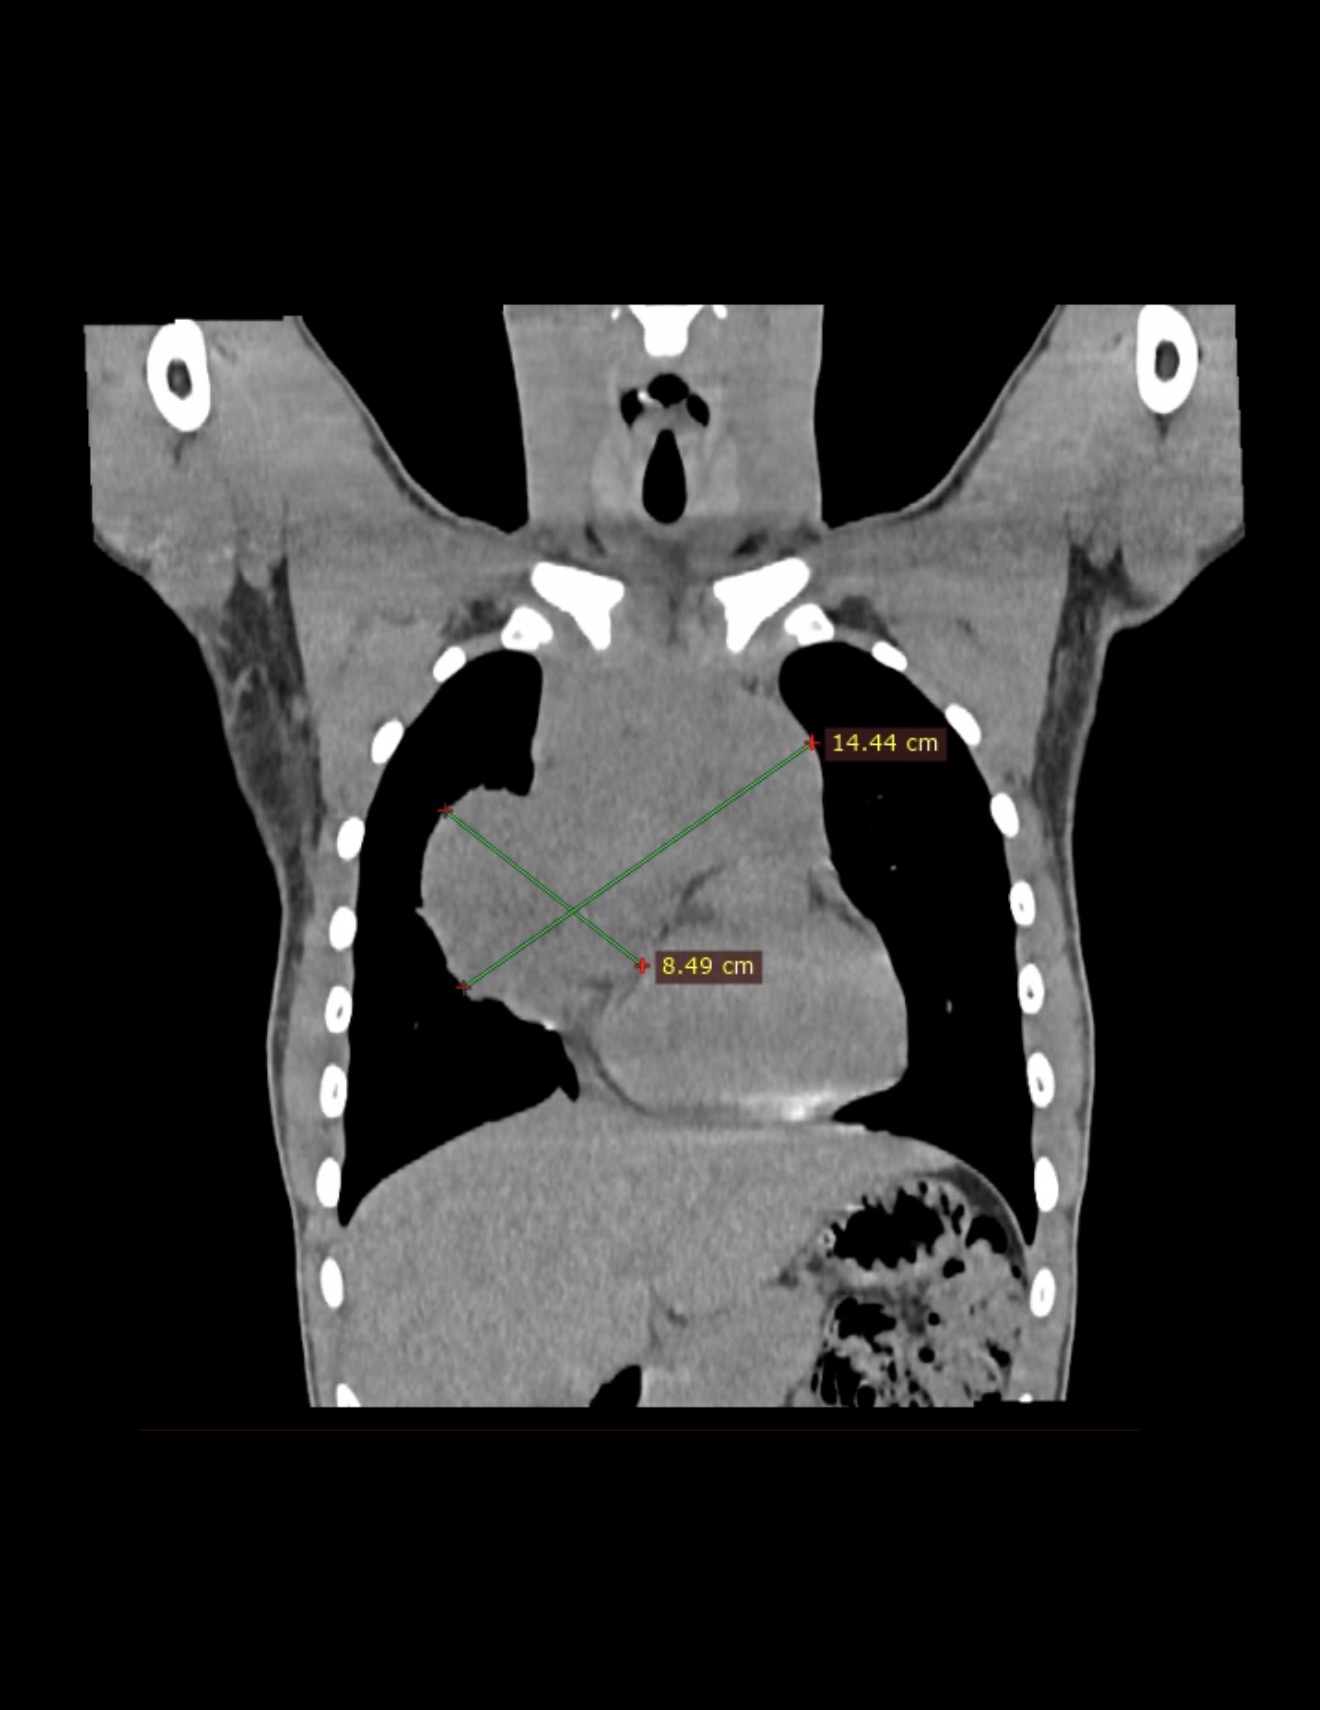

"Пухлини середостіння у дітей — це різноманітні новоутворення (близько 50% складають лімфоми, а також нейрогенні пухлини та тератоми), що часто мають злоякісний характер. Вони проявляються задишкою, кашлем або синдромом Горнера. Діагностика включає КТ, МРТ або УЗД, а лікування часто вимагає комбінації хірургії та хіміотерапії", — зазначають лікарі.

За останній місяць командою торакальних хірургів та хірургів-онкологів було виявлено та успішно прооперовано два складних випадки пухлин середостіння у дітей, інформують на фб-сторінці Вінницької обласної дитячої клінічної лікарні Вінницької обласної Ради.